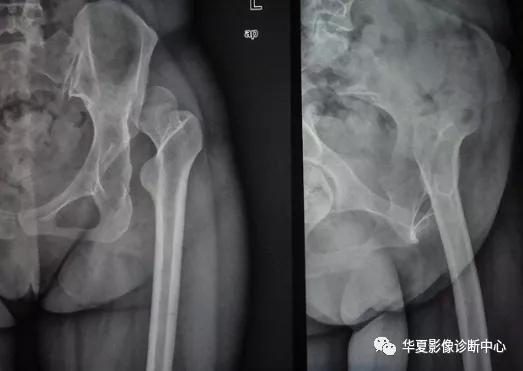

根据Growe分级标准,CDH可分为三期:Ⅰ期,脱位50%以下;Ⅱ期,脱位50%~70%;Ⅲ期,脱位75%~99%。

根据Zionts分级标准,CDH可分为四级(即四度):Ⅰ度为股骨头骺核位于两侧Y形软骨顶点的连线(即Y线)以下而在髋臼外上缘之外;Ⅱ度为股骨头骺核位于Y线与平行于Y线的臼上缘平行线之间;Ⅲ度为股骨头骺核位于臼上缘平行线高度;Ⅳ度为股骨头骺核位于臼上缘平行线以上,并有假臼形成。

临床上一般采用Zionts分级标准,其具有分类清楚、客观性强的优点,对于CDH患者的临床治疗具有十分重要的意义。